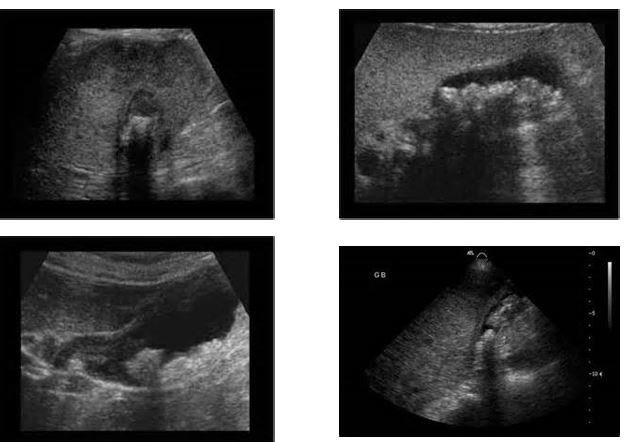

4 pics of Choledochal Cysts

different patterns of cholelithiasis

patterns of sludge